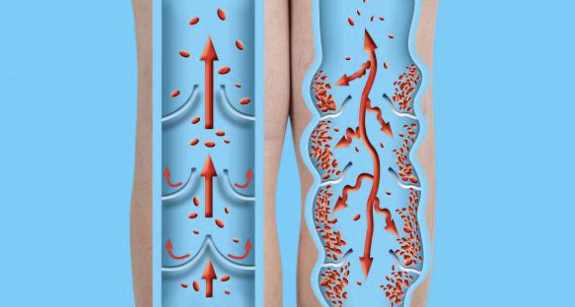

Wanneer aderen extra aandacht verdienen

Soms kan een verandering in aderen wat extra aandacht vragen. Dat kan bijvoorbeeld gebeuren wanneer aderkleppen minder krachtig werken.

Aderkleppen zorgen ervoor dat het bloed in de juiste richting blijft stromen.

Wanneer deze kleppen minder actief zijn, kan de doorstroming wat veranderen. Daardoor kunnen aderen duidelijker zichtbaar worden.

Meer uitleg staat op deze medische informatie.

Dit verschijnsel komt vaak voor in de benen. Veel mensen kennen dit als spataderen.

Regelmatig bewegen en het afwisselen van zitten en staan kan helpen om de bloedsomloop actief te houden.

Een arts kan altijd advies geven wanneer iemand hier vragen over heeft.